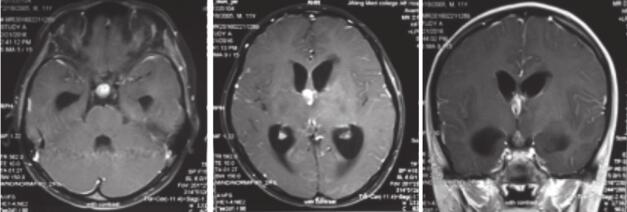

患者,男性,10岁,“发现颅内多发占位1个月,VP分流术后1周”入院。患者于2016年2月7日无明显诱因下出现饭后呕吐数次,呈非喷射性,呕吐物为胃内容物,随后出现嗜睡,精神状态明显下降,期间患者意识清晰,无四肢抽搐,无剧烈头痛及四肢活动障碍等不适主诉。遂至医院行头颅MR提示:鞍上区及左额颞病灶,鞍上病灶强化,伴脑积水,怀疑胶质瘤可能(图1)。给予对症支持治疗后患者症状无明显缓解,呕吐频率增加,性质较前无变化。近两周来,患者开始出现头痛,表现为呈胀痛,以额颞部为著。至儿科医院就诊,给予甘露醇脱水治疗后好转。患者就诊我院后行VP分流术。术后患者症状明显缓解,进一步查脑脊液脱落细胞,示散在淋巴细胞,恶性证据不足,目前为进一步明确诊断入院。入院查体:患者神清,精神可,双瞳等大等圆,对光反射灵敏,眼底检查提示视神经盘轻度水肿,余脑神经检查未见明显异常。四肢肌张力可,肌力正常,腱反射++,病理反射未引出,行走可,共济检查配合欠佳,闭目难立征阴性。

图1 患者术前头颅MR提示鞍上区及左额颞病灶,鞍上病灶强化